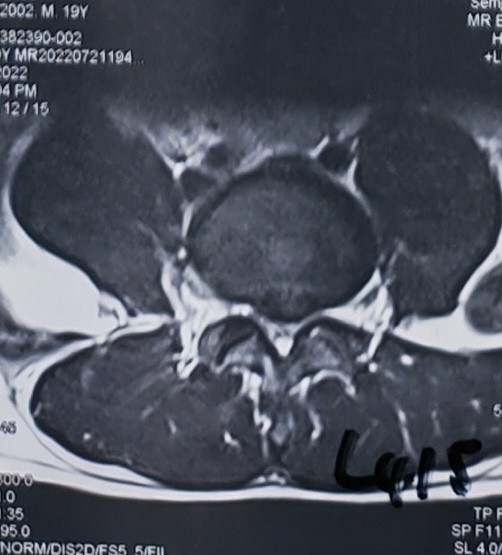

患者男,19岁,高三学生,左下肢疼痛半年,各种保守治疗无效

入院诊断:腰椎间盘突出症(L4/5)